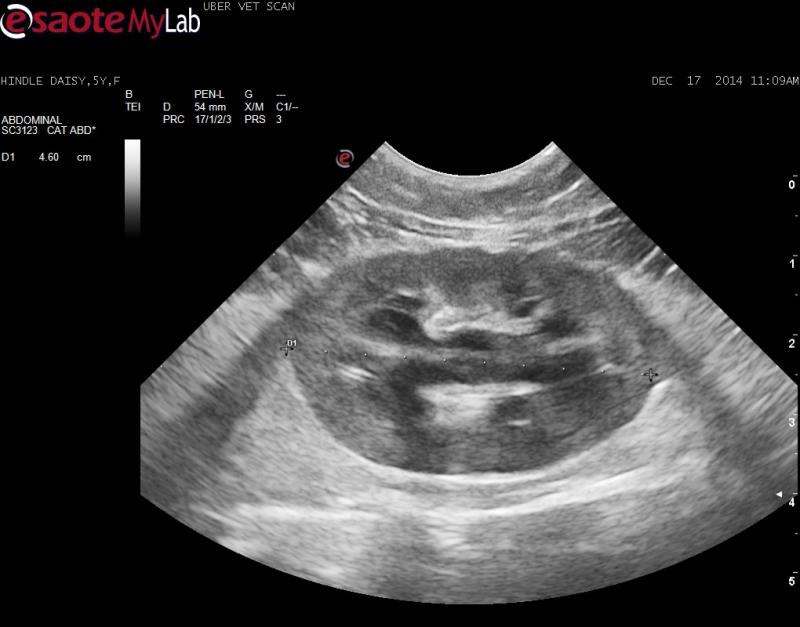

– both kidneys mildly enlarged, surrounded by ill-defined, bright hyperechoic fat and mild pylectasia

– a trace amount of subcapsular fluid noted around the right kidney at the caudal pole (second clip shows this)

Yep those are painful just looking at them with all that inflamed peripheral fat. Acute nephritis/pyelonephritis, infectious, toxin, FIP, Early lsa can look like this especially on your second clip.

$ case?? I’m getting a 25 g needle into the cortex of the kidney in the second clip and looking for mixed population (nephritis… also FIP will be mixed but granulomatous but I can;t tell the difference wiht my cyto skills) vs monopopulation of lymphoma cells. If no lsa then tx for ARF/nephpritis 72 hours and see where you go. maybe cover for toxo.. baytril clindamycin my shotgun choice here.

1. The capsule also looks very irregular. Does this help sort out the pathology?